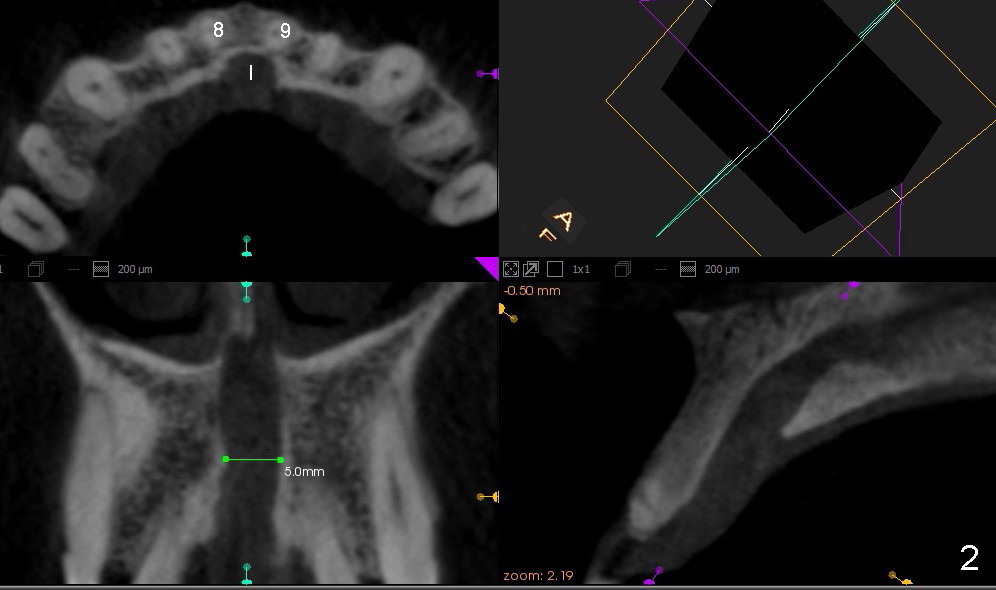

CT研究表明当切牙管小时(图一:I(Incisive Canal),二毫米左右),它比较对称,位于中切牙牙根之间(8,9)。当它大时(五六毫米),它可能对称(图二)或者不对称(图三,四),接近一个(图三,四)或者两个(图二)牙根,造成植牙困难。